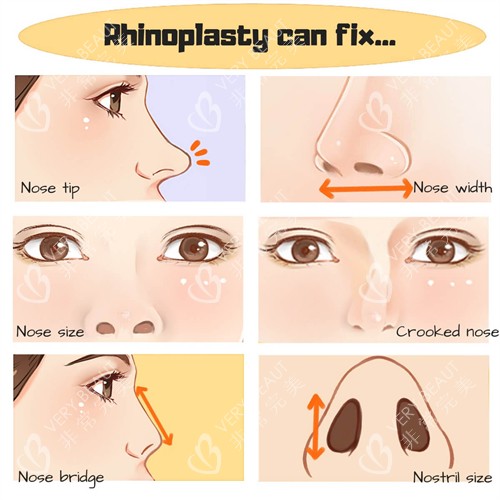

后来刷小红书,看到有人分享张辉医生的鼻修复病例,里面有个姑娘跟我一样是“假体透光+鼻头歪”,术后3个月的照片里,鼻子又自然又立体,完全看不出修复痕迹。我赶紧约了面诊,心里还打鼓:不会又是网上的“照骗”吧?

面诊那天,张医生的诊室里放满了病例册,不是模糊的网图,全是他自己做的鼻修复顾客,从术前到术后1个月、3个月、半年的修复图都有。有个姑娘跟我眼型、鼻基底差不多,术前假体透光严峻,术后鼻梁自然得像天生的,连鼻头的弧度都跟脸型特别搭。

现在3个月过去,鼻子完全消肿,摸起来软软的,跟天生的没区别。上周我素颜去菜市场买菜,卖菜阿姨还说“姑娘你鼻子真好看”;拍照更别提了,正面、侧面拍都很立体,朋友圈发照片再也不用P鼻子。

回头看这一路,我特别庆幸选了张辉医生——他没让我白遭罪,还帮我找回了敢素颜出门的自信。其实鼻修复不可怕,可怕的是找错医生,把鼻子越修越糟。

如果你们也跟我一样,被隆鼻失败困扰,不妨跟张医生聊聊,说不定也能像我一样,摆脱烦恼,拥有自然的鼻子。记住,鼻修复是“救鼻子”的大事,一定要找正规、有真病例、不忽悠的医生,才是对自己负责。